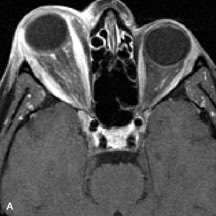

Tl relaxation time is the time required for the energized nuclei to give up the excess energy that was acquired from the RF pulse (high-energy state) and re-establish equilibrium (low-energy state) with the main magnetic field. The excess energy is released by these excited nuclei to the surrounding molecular environment, or lattice, and results in T1 relaxation, also called spin-lattice relaxation time. In different biologic tissues, hydrogen has a Tl ranging from a few hundred milliseconds to a couple of seconds. This range exists because local tissue factors affect the ability of specific protons to give up energy to the surrounding tissues. For example, hydrogen atoms attached to the carbon atoms of fat molecules relax much more rapidly than those attached to the oxygen atoms of water molecules. Viscosity, concentration, temperature, and molecular environment of the hydrogen atoms in the tissues also affect the T1 relaxation time. On a T1-weighted orbital image, fat, which has a very short T1 relaxation time, yields a high-intensity signal; the rectus muscles, which have an intermediate T1, yield an intermediate-intensity signal; and the vitreous, which has a long T1, yields a low-intensity signal (Fig. 8).5,8,16

Fig. 8. T1-weighted image shows the excellent contrast resolution of the soft tissues of the orbit. Note the contrast between the high-intensity (bright) signal of orbital fat and intermediate signal of the extraocular muscles and optic nerves. The lens, vitreous, and sclera can also be easily distinguished. The air in the ethmoidal sinuses emits no signal and therefore appears dark (arrow-head). The left lateral orbital wall also appears dark because of the low proton density and free-water content of cortical bone (short arrows). The bone marrow in the right orbital rim is depicted by a bright signal as a result of its fat contents (long arrow). (Dortzbach RK, Kronish JW, Gentry LR: Magnetic resonance imaging of the orbit. Part II. Clinical applications. Ophthal Plast Reconstr Surg 5:161, 1989)

NORMAL ORBITAL ANATOMY

T1-weighted images provide the best anatomic details of the orbit because they display superior contrast resolution between normal structures (see Fig. 8). The vitreous has a long T1, resulting in an intermediate signal similar to brain, whereas the crystalline lens and sclera appear dark because of a longer T1 and short T2. The extraocular muscles, like all skeletal muscles, demonstrate a moderately long T1 and short T2 and highly contrast with the intense signal of the surrounding orbital fat (adipose tissue has an extremely short T1). The lacrimal glands appear as mottled areas of reduced intensity of the signal from the orbital fat in the lacrimal fossa. The optic nerves are seen with the same signal intensity as brain white matter and are hypointense relative to the orbital fat because their Tl is longer than the Tl of fat but shorter than the Tl of water.